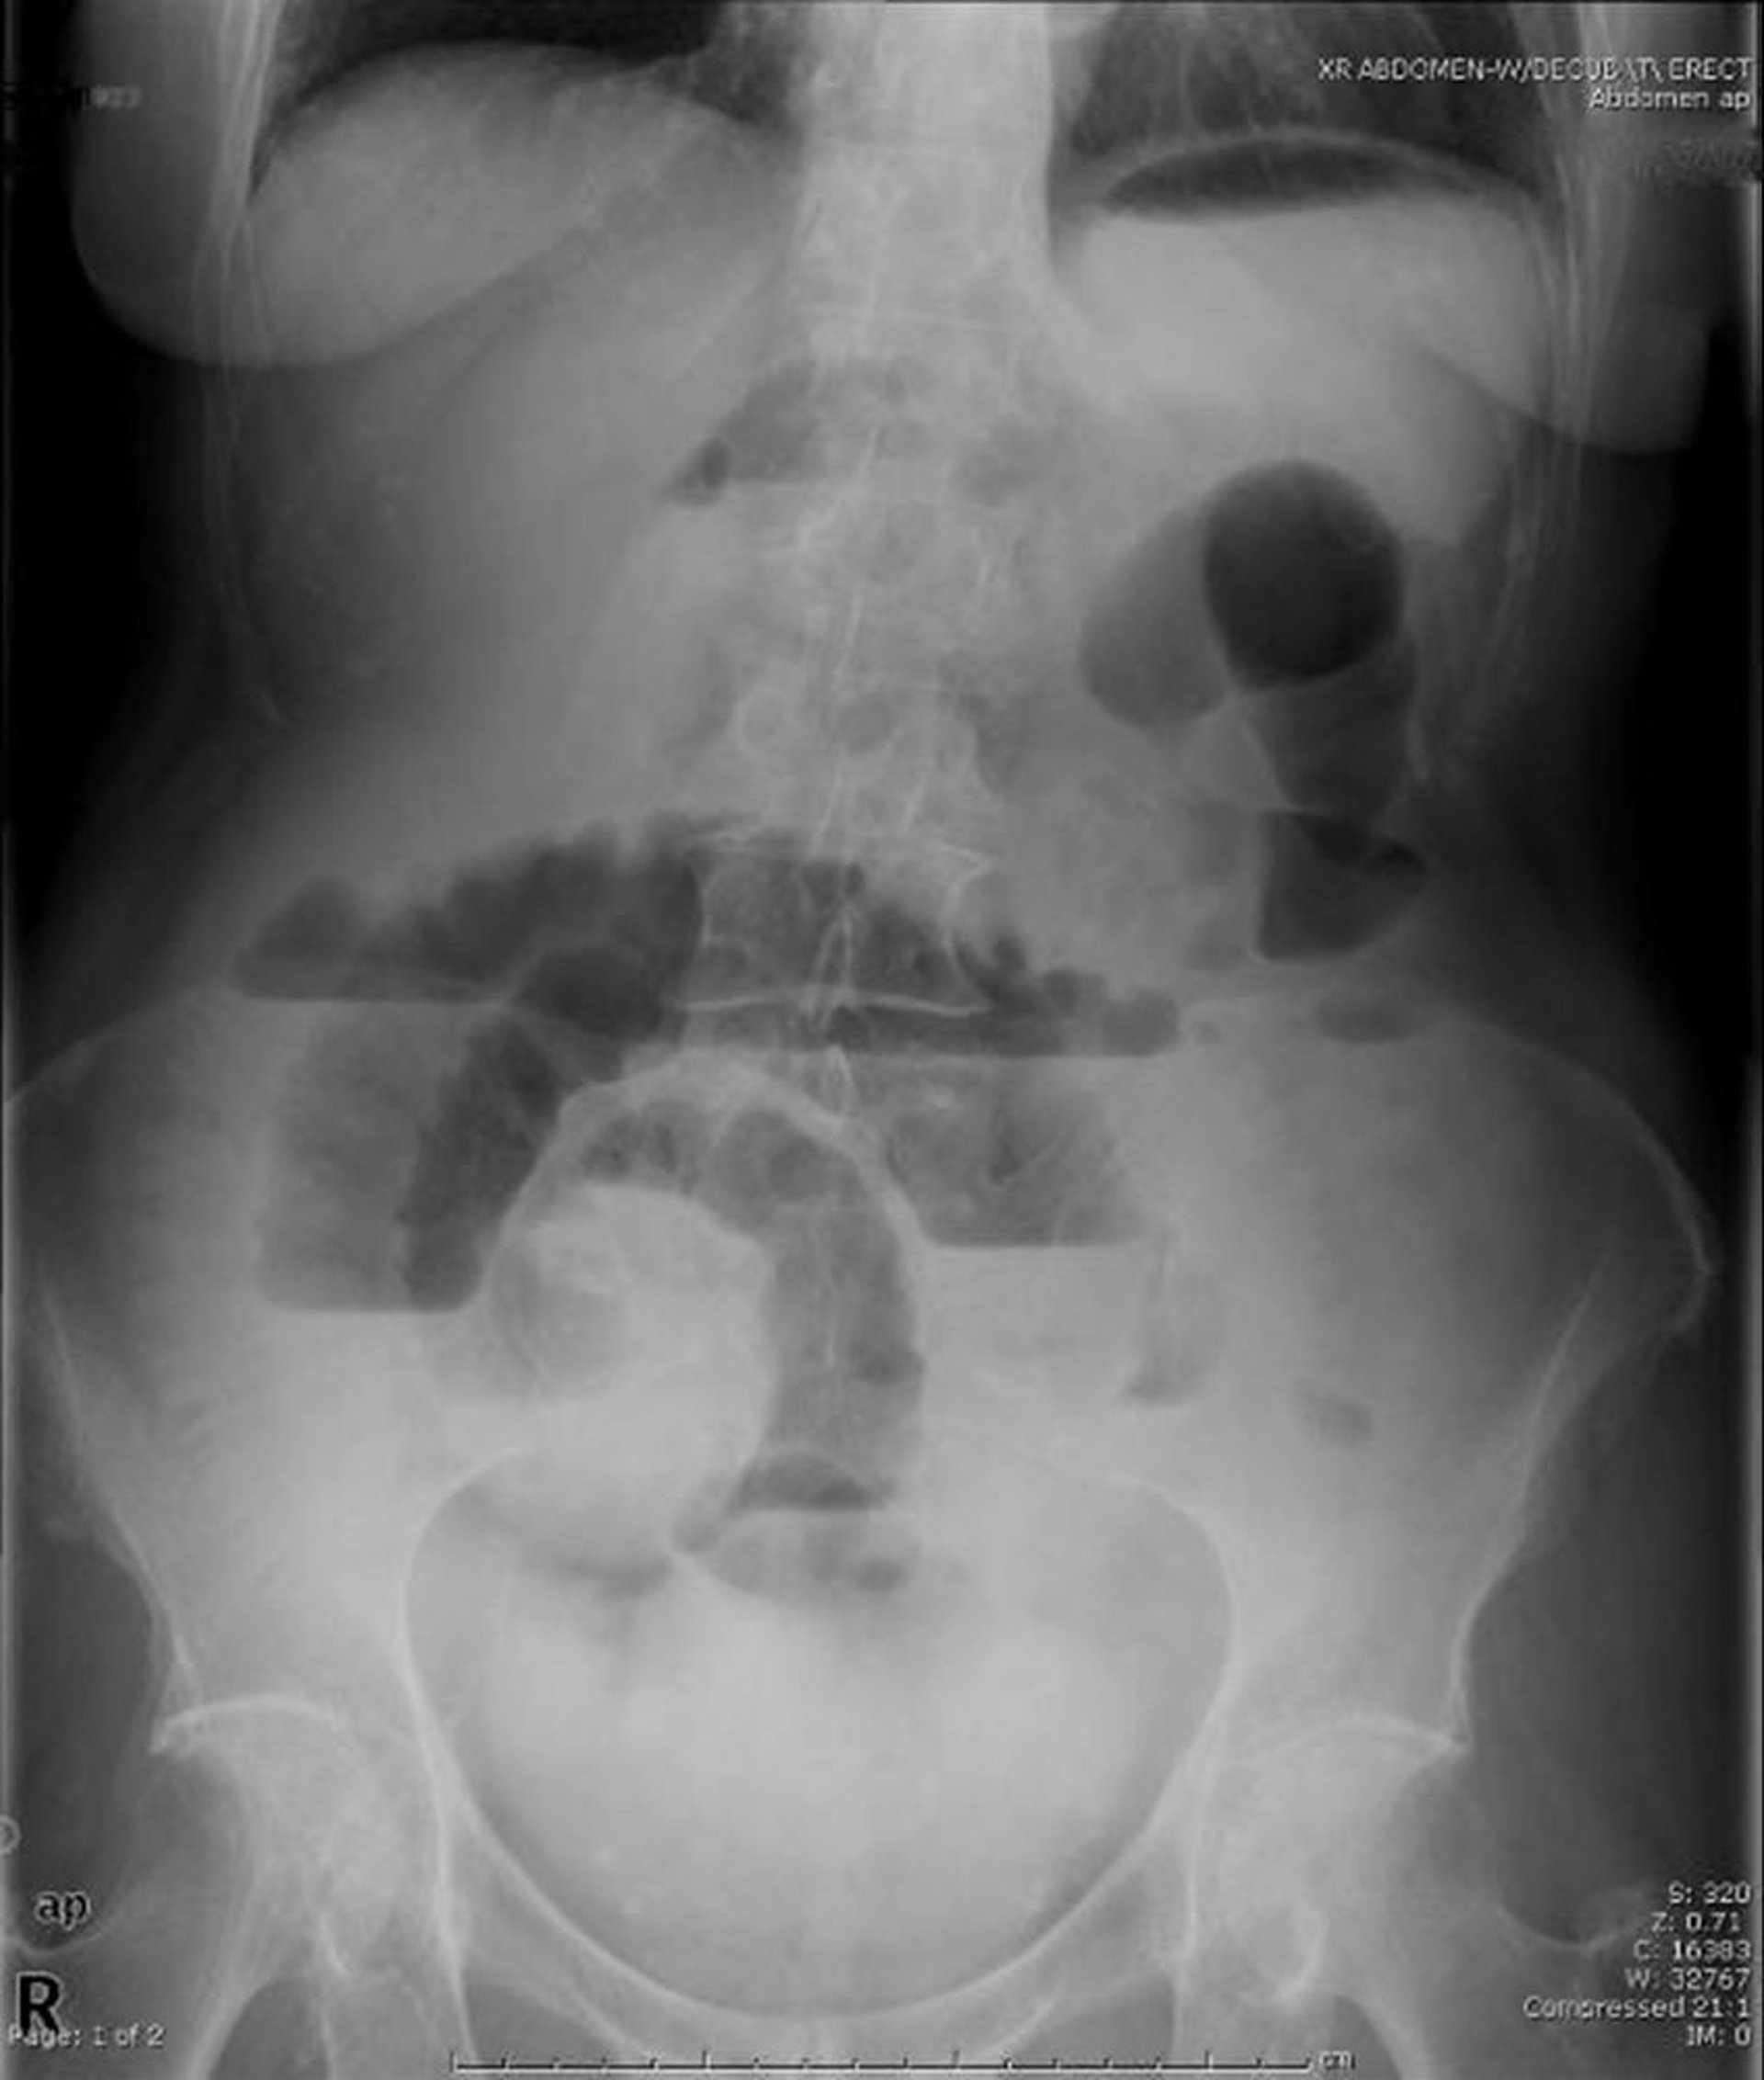

Tắc ruột non (phim chụp X-quang tư thế đứng thẳng)

Phim chụp X-quang bụng tư thế đứng thẳng này cho thấy tình trạng tắc ruột non. Thấy có nhiều mức dịch-khí.